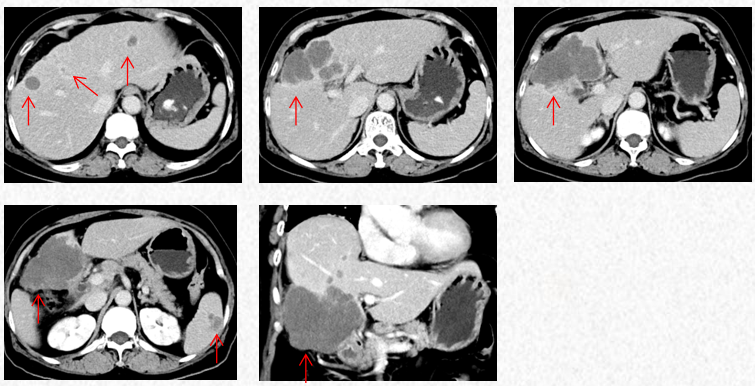

2023-7-15复查胸腹CT图片,疗效评估为SD,轻度双上肢麻木,生活不受影响。

2023-7-15胸腹CT:肝肿物最大横截面积86*58mm,脾脏转移瘤(19*12mm)